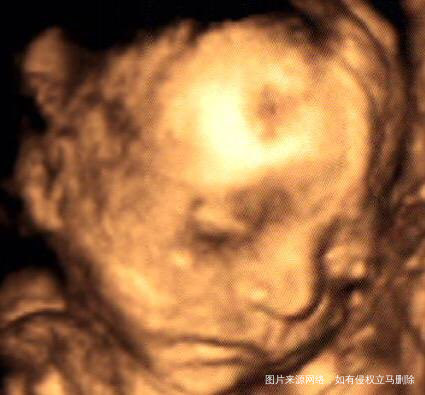

接健康帅气宝宝,你这四维照片好清楚啊,多少周做的?

游游 回复 六宝:二十三周加五天,😄

五官长得很好👍

游游 回复 好运常伴_643646:女儿像爸爸,和他爸爸很像